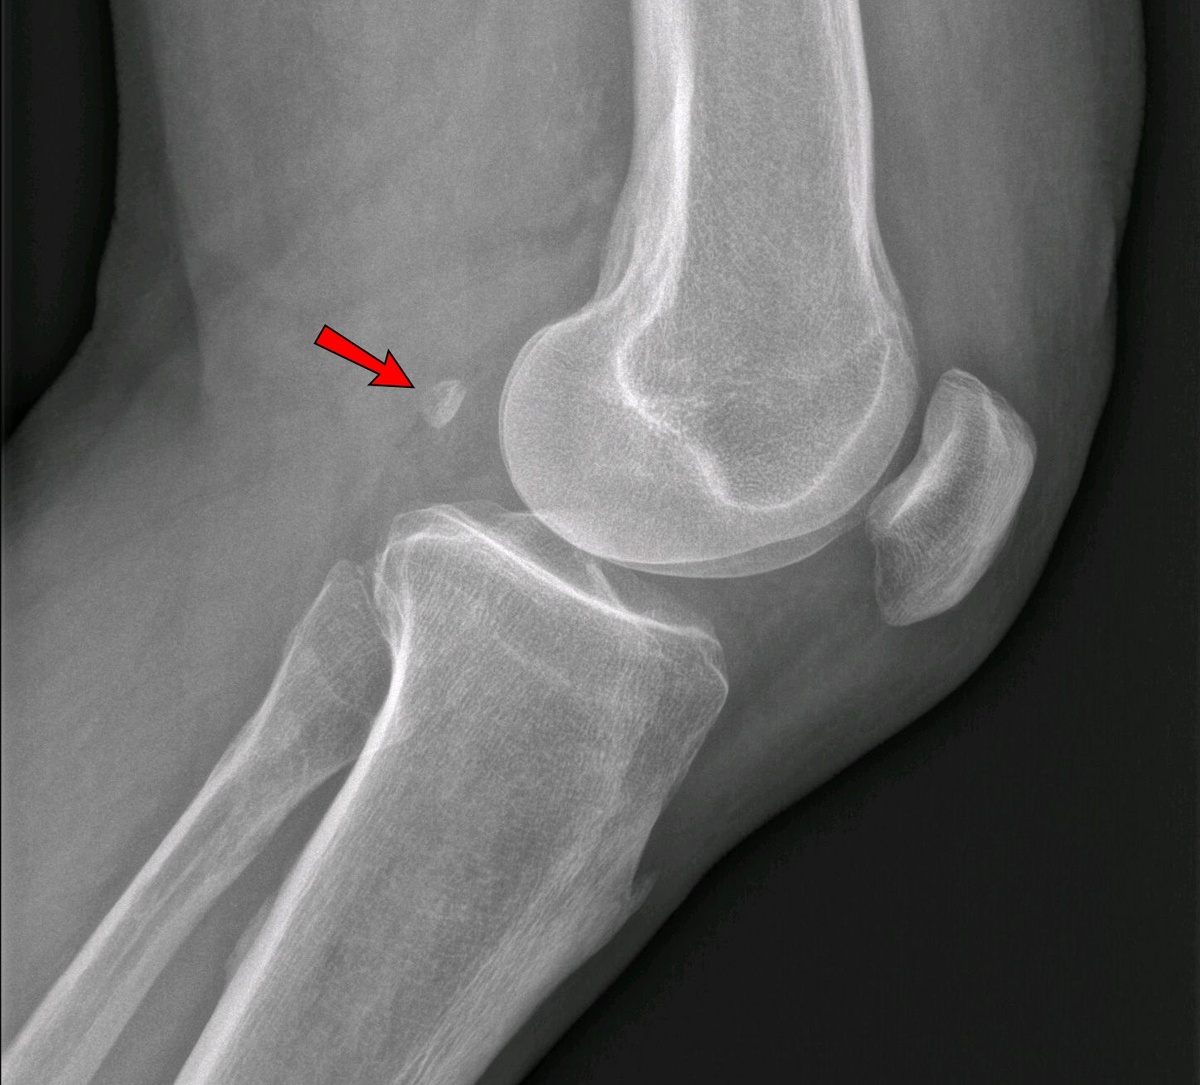

Это фабелла! Маленькая коленная сесамовидная кость, которая есть у большинства приматов и у 10-30% людей. Кстати, fabella – уменьшительное от faba, что с латинского переводится как «фасоль».

Искать фабеллу, как и другие сесамовидные кости, нужно в толще сухожилий, у человека – с задней стороны колена. У приматов она может увеличивать механическую эффективность коленного сустава. А у людей в ходе эволюции фабелла почти исчезла, но в последнюю сотню лет у неё случился камбэк.

Встречается фабелла чаще у мужчин, чем у женщин, чаще у пожилых, чем у молодых, а также у людей с остеоартритом коленного сустава. Эта косточка может вызвать дискомфорт. Есть даже «синдром фабеллы» (заднебоковая боль в колене).